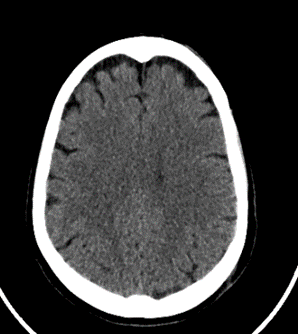

Existen casos donde podremos observar un aumento del espacio subaracnoideo lo cual no debe informarse como patológico o como atrofia yo que el mismo puede simplemente deberse a un hallazgo de naturaleza constitucional.

En relación con la atrofia cortical que es propia de los pacientes añosos, esta no debe confundirse con higromas o hematomas subdurales crónicos.

Fig. 7.